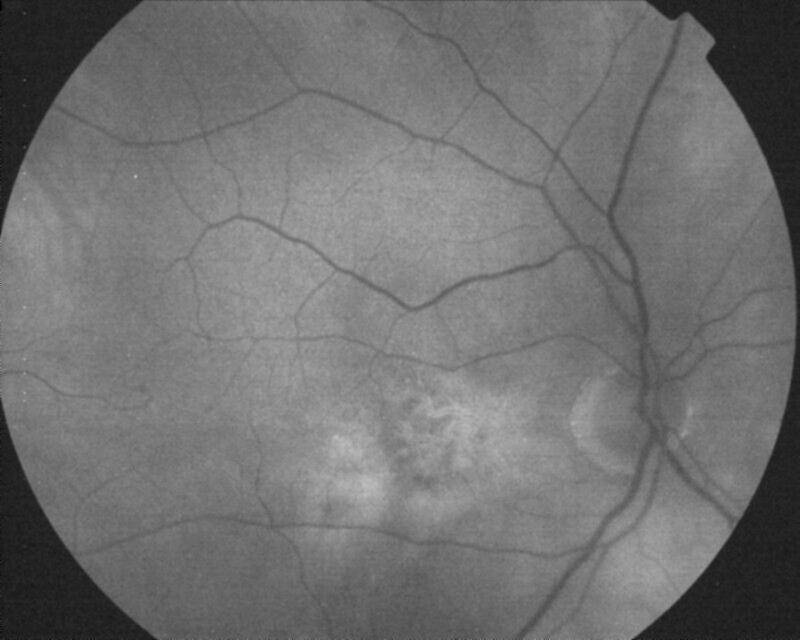

ATROPHIE AREOLAIRE CENTRALE